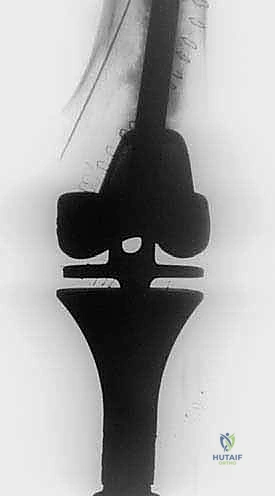

Despite meticulous technique, cryosurgical ablation carries a distinct and significant complication profile. As academic surgeons, we must counsel our patients transparently and be prepared to manage these complex sequelae. The most common and devastating complication is a postoperative pathological fracture. The incidence of fracture ranges from 5% to 15%, depending heavily on the anatomical location, the size of the cortical window, and the adequacy of prophylactic fixation. The profound thermal necrosis weakens the bone significantly, and the necrotic phase peaks between 4 to 8 weeks postoperatively, making this the highest-risk window for structural failure. Salvage management for a fracture typically involves revision open reduction and internal fixation (ORIF), often requiring longer spanning plates, structural allografts, or in severe cases of joint collapse, conversion to a megaprosthesis or total joint arthroplasty.